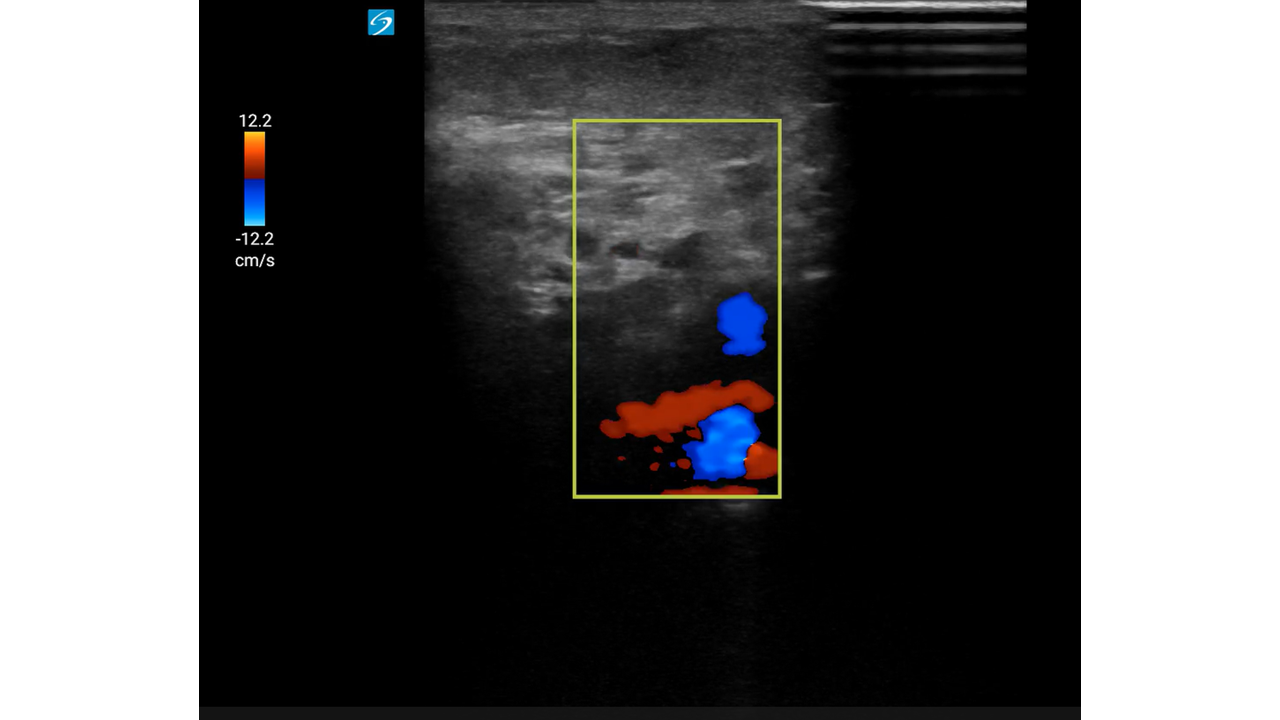

Mujer de 93 años con: fibrilación auricular, enfermedad renal crónica y antecedentes de hemorragias digestivas por las cuales se le había suspendido la anticoagulación oral meses antes.

Motivo de consulta: Dolor súbito, frialdad y pérdida de sensibilidad en la extremidad inferior derecha (EID), con mejoría parcial durante el traslado.

Con sospecha inicial de Isquemia Arterial Aguda (IAA), la mejoría clínica hace dudar abriendo el diagnóstico diferencial a una posible radiculopatía.

Con sospecha clínica de IAA, la ecografía vascular es clave para confirmar el diagnóstico. Su curva de aprendizaje es rápida, se puede utilizar en cualquier punto del sistema y permite derivar al paciente a un centro útil evitando demoras potencialmente fatales.